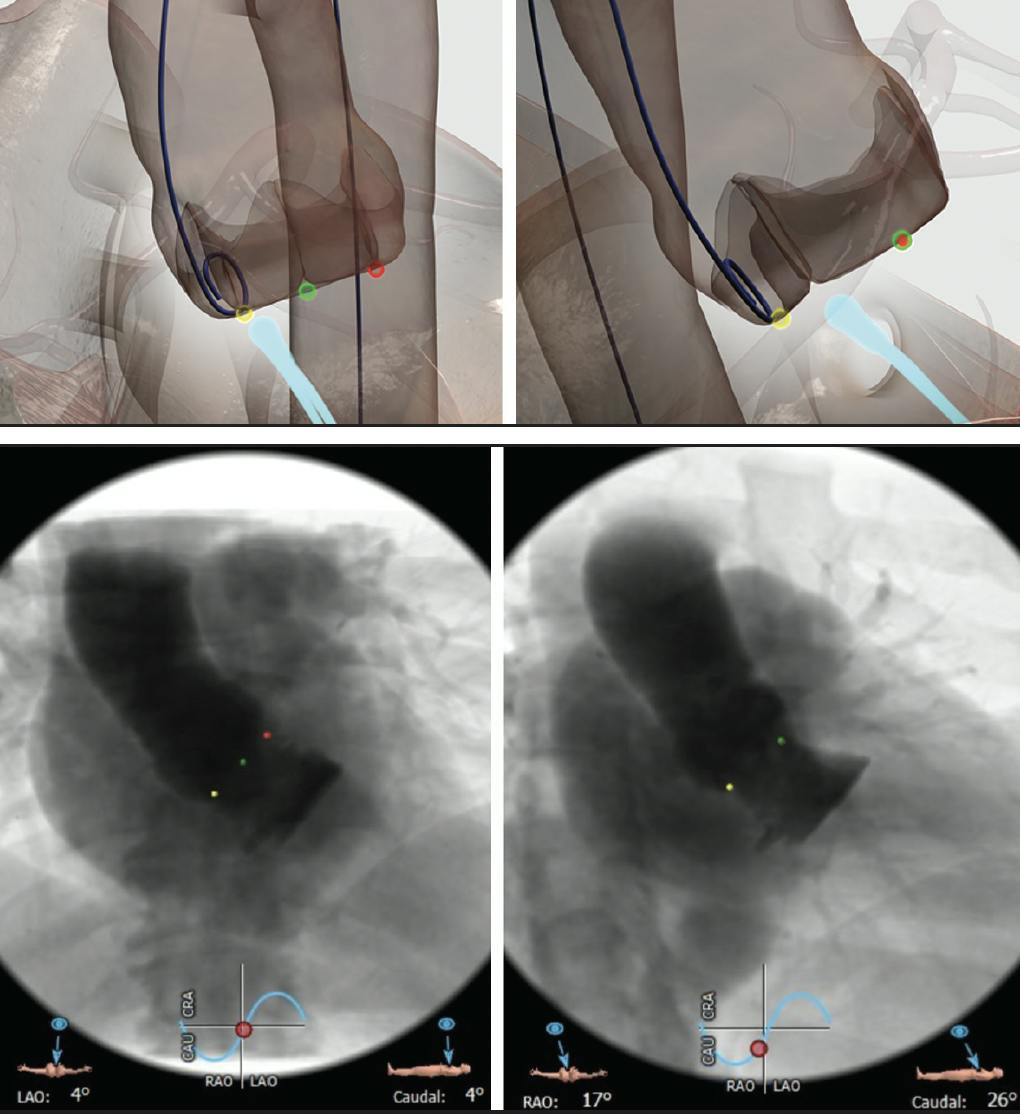

Before complete deployment of the Evolut Pro THV, the depth should be checked in both views by injecting contrast (Figure 4). In the noncoronary cusp, the implantation depth might appear shallower in the left anterior oblique (LAO) view and should therefore only be evaluated in the cusp overlap view.

Figure 4. Evaluation of implantation depth at the noncoronary cusp in the cusp overlap view (left side) and at the left coronary cusp in the LAO view (right side).